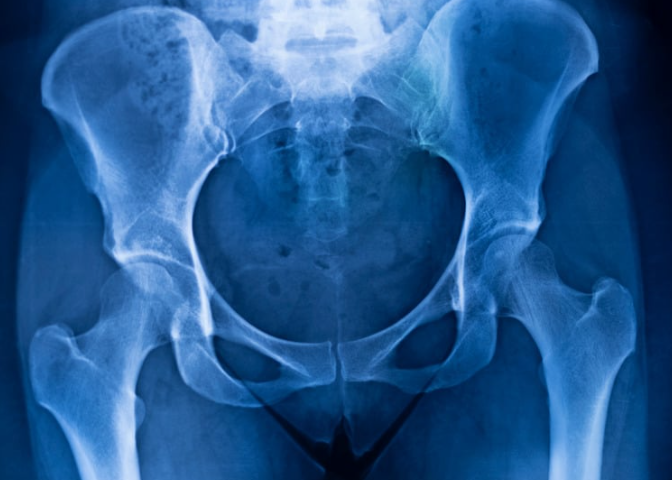

Her MRI was clear — no labral tear. That was good news.

1️⃣ Accurate Diagnosis

First, we determine:

- External vs internal vs intra-articular

- Is it painful or just audible?

- Is there tendon irritation?

- Do we need imaging?

A proper assessment prevents misdiagnosis.